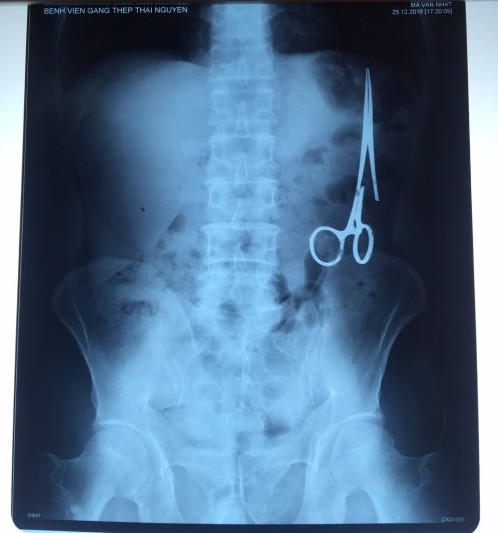

遺留在病人腹中的剪刀

據(jù)越南青年報1月2日報道,在越南首都河內(nèi)醫(yī)療專家的幫助下,越南東北部的太原省(Thai Nguyen)鑄鋼醫(yī)院的醫(yī)生日前從54歲患者M.V.N腹中取出一把醫(yī)用剪刀。這把剪刀是此前曾為M.V.N手術(shù)的醫(yī)生遺留的,已經(jīng)在其腹中待了18年時間。

醫(yī)務(wù)人員表示,這把剪刀遺留在病人腹部左側(cè),與結(jié)腸緊挨著。剪刀的把手已經(jīng)生銹,部分器官也已經(jīng)與剪刀粘連起來。但在過去多年中,M.V.N沒有任何不適感覺,也從未因為留在腹中的剪刀引發(fā)的相關(guān)問題去看過醫(yī)生。直到2016年12月,M.V.N因為遭遇了一場車禍,才到鑄鋼醫(yī)院進行身體檢查。

超聲波檢查顯示,M.V.N的腸子中有個奇怪物體,看起來就像醫(yī)用剪刀。M.V.N證實,他曾于1998年6月份在北江省綜合醫(yī)院接受手術(shù),在此后也從未進行過任何手術(shù)。近來,他感到腹部有些疼痛,并試圖通過服用藥物治療。12月27日,M.V.N回到北江省綜合醫(yī)院再次進行超聲波檢查,顯示其腹部的確存在怪異物體。